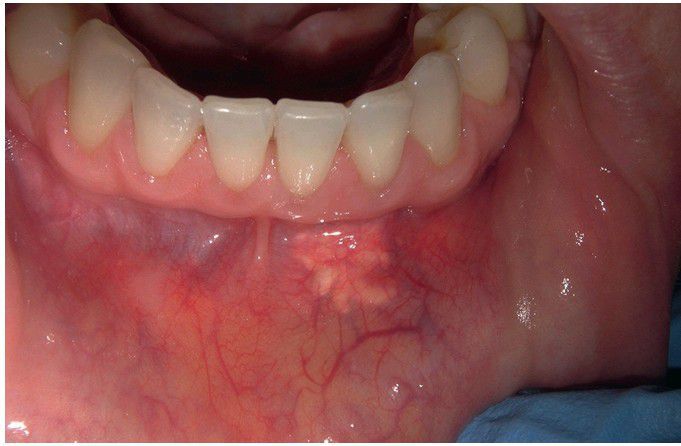

Cosmetic Filler Material.

Yellow submucosal mass of the mandibular labial vestibule. Biopsy revealed hydroxyapatite (Radiesse) with fibrosis and granulomatous inflammation.